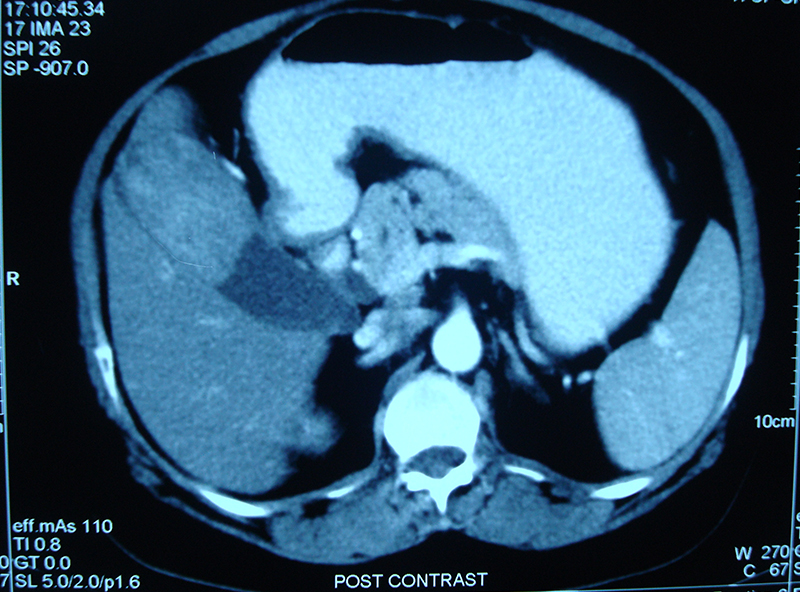

45 year old lady with abdominal pain, loss of appetite and weight was diagnosed on investigations to have a large gall bladder mass. She underwent a curative radical resection involving the gall bladder, part of liver, bile duct and lymph nodes. The bile duct was joined to a loop of intestine. The opened specimen of gall bladder showed a large mass and multiple gall stones. The mass was a gall bladder cancer (adenocarcinoma) on final histopathology. Patient continues to live happily for more than 5 years after surgery without any chemotherapy. To know more about gall bladder cancer click here